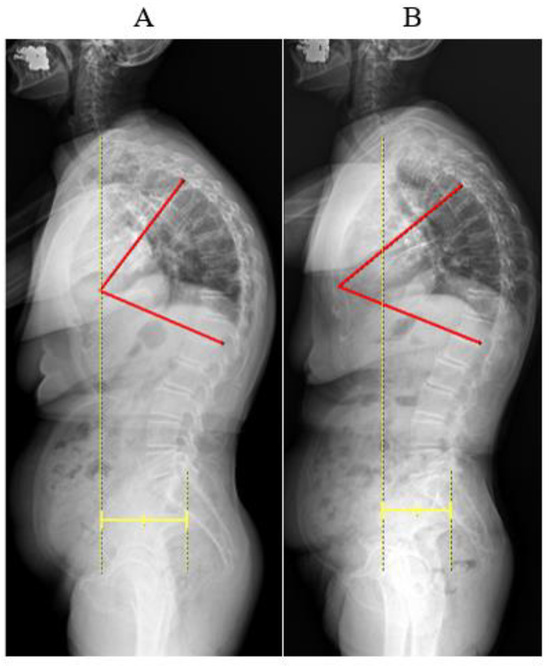

| Radiographic Index | Range of Thoracolumbar motion (degree) | |||||

|---|---|---|---|---|---|---|

| TK (°) | SVA (mm) | Flexion | Extension | Lat. Bending (Rt./Lt.) | Rotation (Rt./Lt.) | |

| Week 1 | 77.7 | 95.55 | 60 | 10 | 10/10 | 45/45 |

| Week 3 | 61.1 | 77.84 | 60 | 20 | 15/15 | 45/45 |